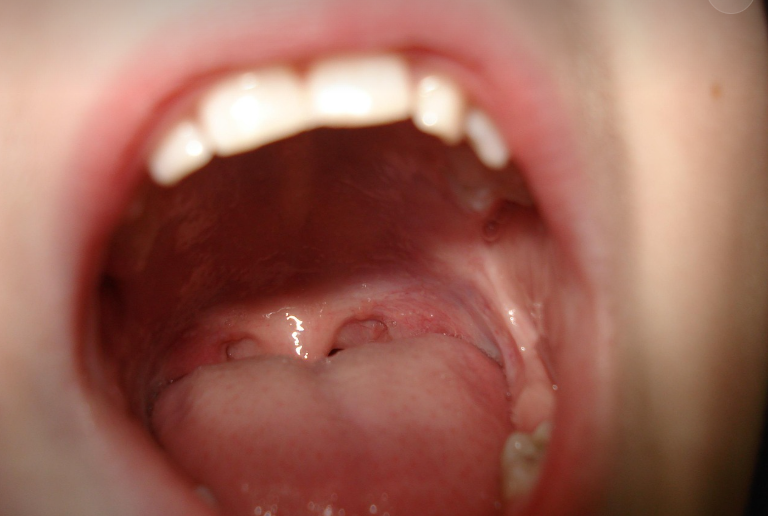

구내염은 입안의 점막에 염증이 생기는 질환으로, 통증과 불편함을 유발하는 흔한 증상입니다.

주로 볼 안쪽, 혀, 입천장, 잇몸 등에 발생하며, 자연적으로 치유되기도 하지만

심한 경우 전문적인 치료가 필요할 수도 있습니다.